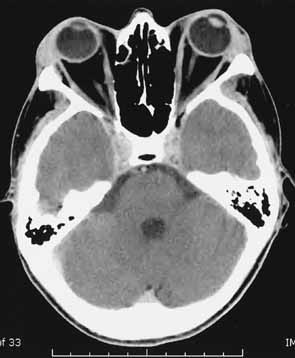

The increased orbital volume is usually due to both extraocular muscle and orbital fat expansion; however, patients younger than 40 years of age are more likely to exhibit orbital fat enlargement in the absence of muscle enlargement, whereas patients over 70 years are more prone to severe, fusiform muscle enlargement without significant changes in orbital adipose tissue volume.49 Forbes et al.11 reported enlargement of the fat compartment in 46% of patients with TO, whereas 8% had increased fat compartments with normal muscle volumes (Fig. 4).

Fig. 4 Axial CT scan of patient with thyroid orbitopathy, extreme proptosis, and no clinical evidence of optic neuropathy. Note the increase in orbital fat volume without significant extraocular muscle enlargement. In this case axial proptosis has allowed spontaneous decompression of increased orbital volume.